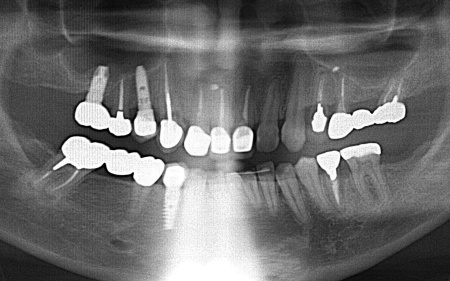

レントゲン撮影をして痛みの原因を詳しく検査したところ、左上下奥歯の歯根が割れており、その影響で痛みが出ていると考えられました。

しかし、レントゲン検査だけでは確実に歯根が割れているかどうかを確定することができません。

以上のことから、温存が難しいと判明している左上奥歯は抜き、左下奥歯は被せ物を取り外して内部を確認したうえで、適切な処置を行うことが望ましいと診断しました。

患者様は、以前当院で人工歯根を顎の骨に埋入して歯を装着するインプラント治療を受けていたため、今回も左上下奥歯ともインプラント治療を希望されています。